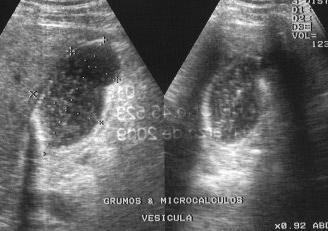

Vesícula biliar

La colecistitis es una enfermedad que consiste en una inflamación de la vesícula biliar que generalmente va acompañada casi siempre de otra inflamación de los conductos biliares.Existen distintas causas que pueden provocar una colecistitis como son los excesos de comida a base de una alimentación tóxica, la presencia de cálculos que faciliten la aparición de agentes infecciosos y nocivos en la vesícula o agentes infecciosos que pueden proceder del intestino o de la sangre.La persona que sufre de colecistitis presenta dolores muy fuertes que se localizan en la zona superior y derecha del abdomen, los cuales se pueden irradiar hacia el hombro derecho. Puede acompañarse de fiebre, náuseas y vómitos.Sigue leyendo porque te contamos cómo tratarla.